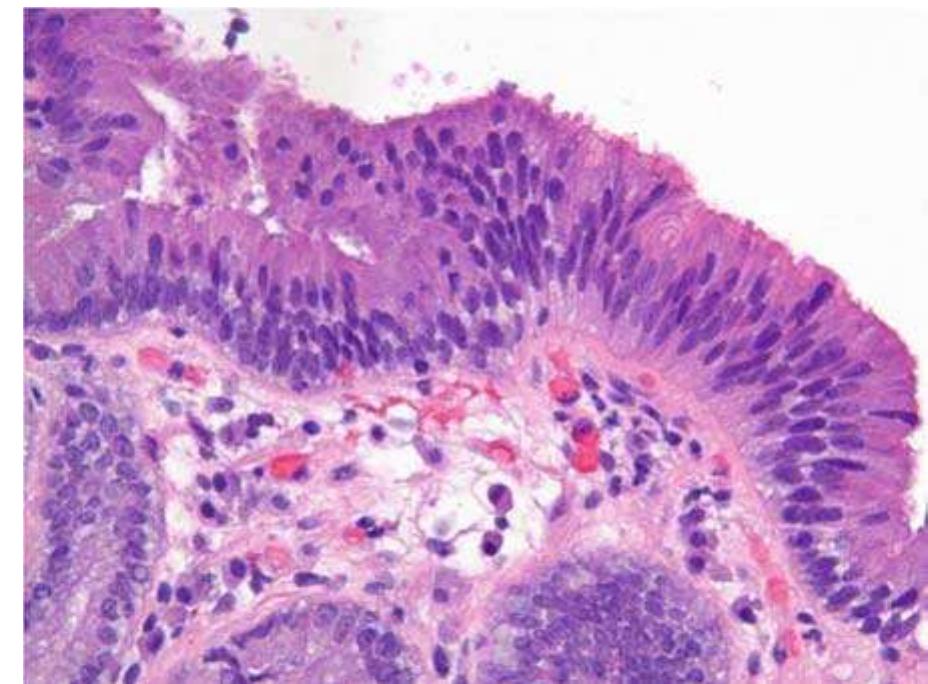

Multiphoton microscopy has become a powerful imaging method for minimally invasive evaluation of extracellular matrix (ECM) and cellular structures deep within tissues in their native environments. This technology, which uses ultra-short... more

Multiphoton microscopy (MPM) is a laser scanning microscopy technique that can provide high resolution, label-free images of living tissues in their native environment that closely resembles the histological sections. In skin, several... more